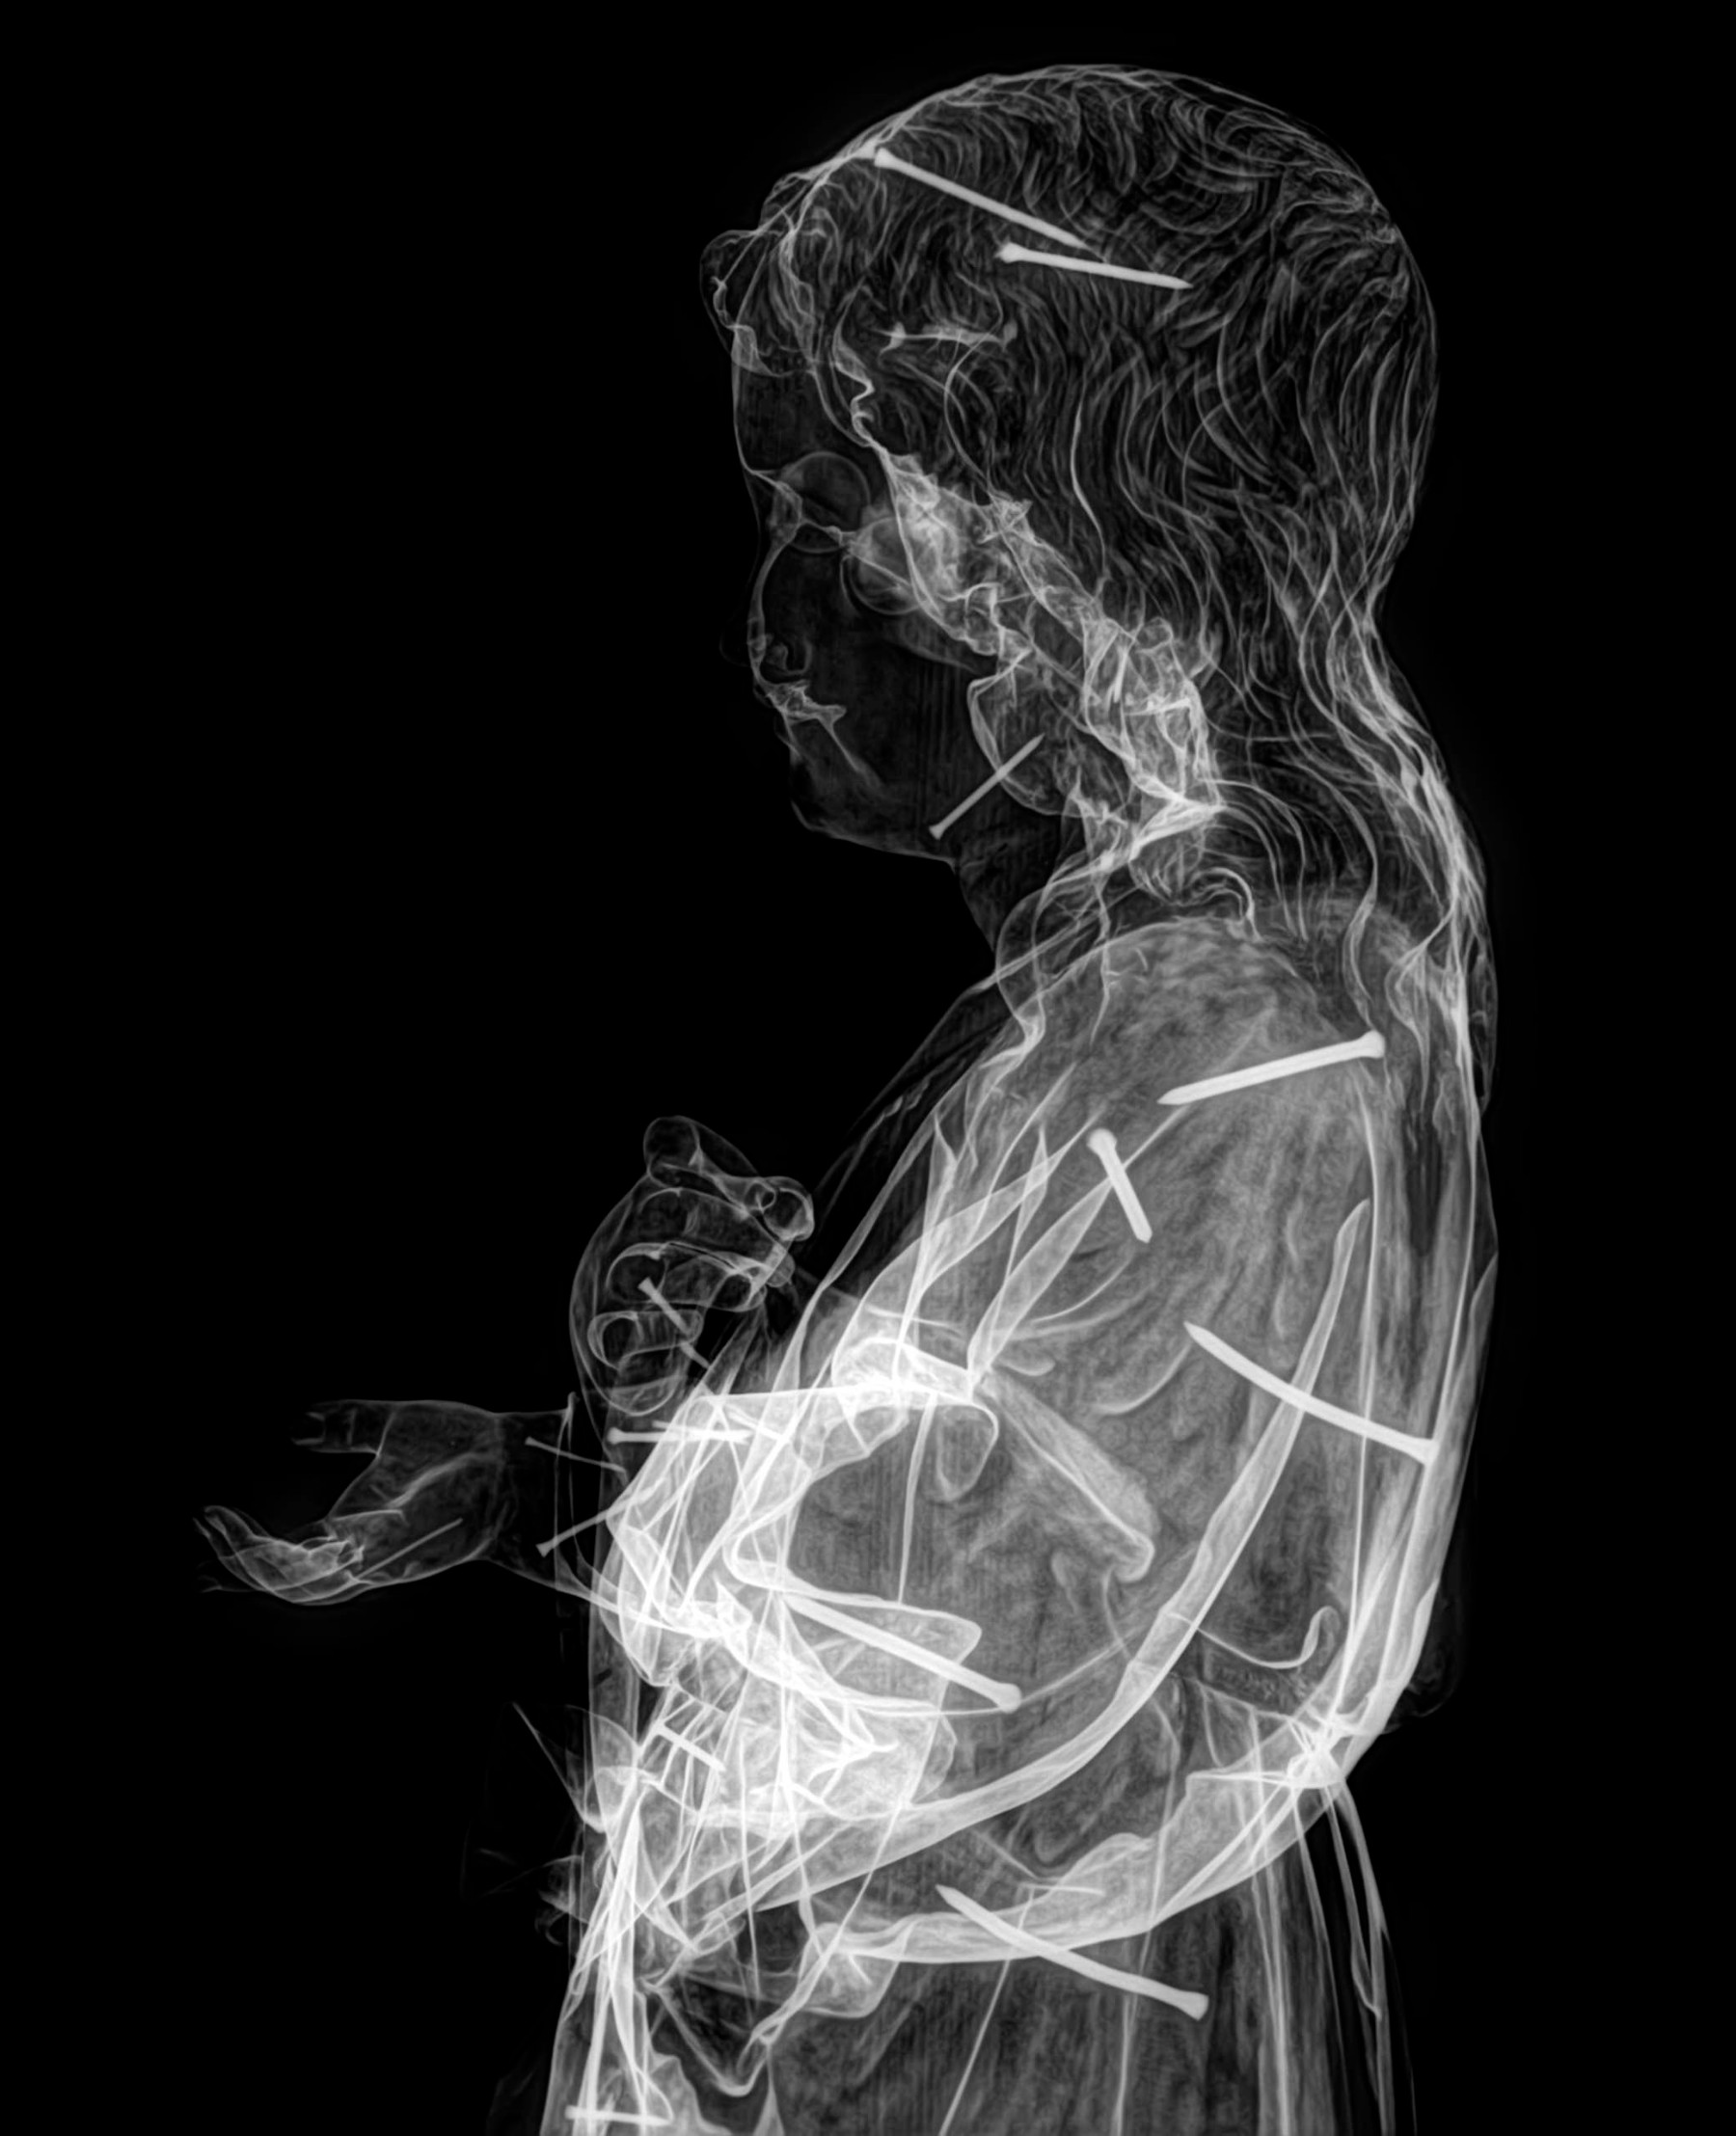

Radiología Digital como Herramienta Complementaria en el Dictamen de Bienes Muebles

Desde el descubrimiento de los rayos “X” y las placas radiográficas por Wilhelm Conrad Roentgen y su posterior difusión a través de la Asociación Físico médica de Wurzburg el 28 de diciembre de 1895, que fue la primera asociación que habló de los nuevos rayos que podían penetrar el cuerpo y fotografiar los huesos, ha habido muchos cambios tanto en la forma de obtener, procesar e incluso en la forma de visualizar, manejar y almacenar las placas radiográficas.